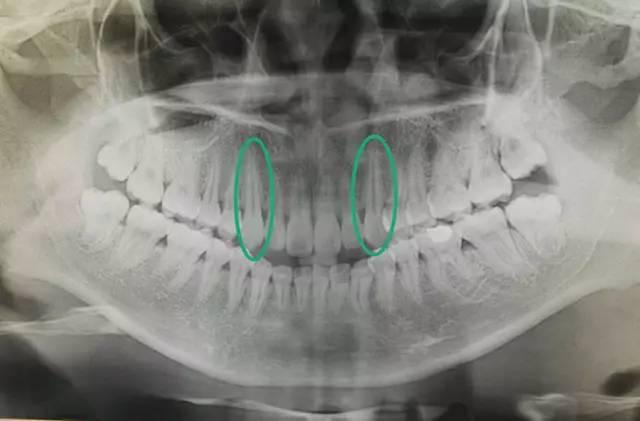

如图,尖牙是所有牙齿当中牙根最长的

更重要的是,尖牙位于口角处,有支撑唇部形态作用,微笑时就能看到,拔掉尖牙可能发生“嘴瘪”,也就是嘴角处的唇部显得塌陷。这也是为何矫正牙齿时,一般选择拔掉第四或第五颗牙齿(位于尖牙后面)的原因。